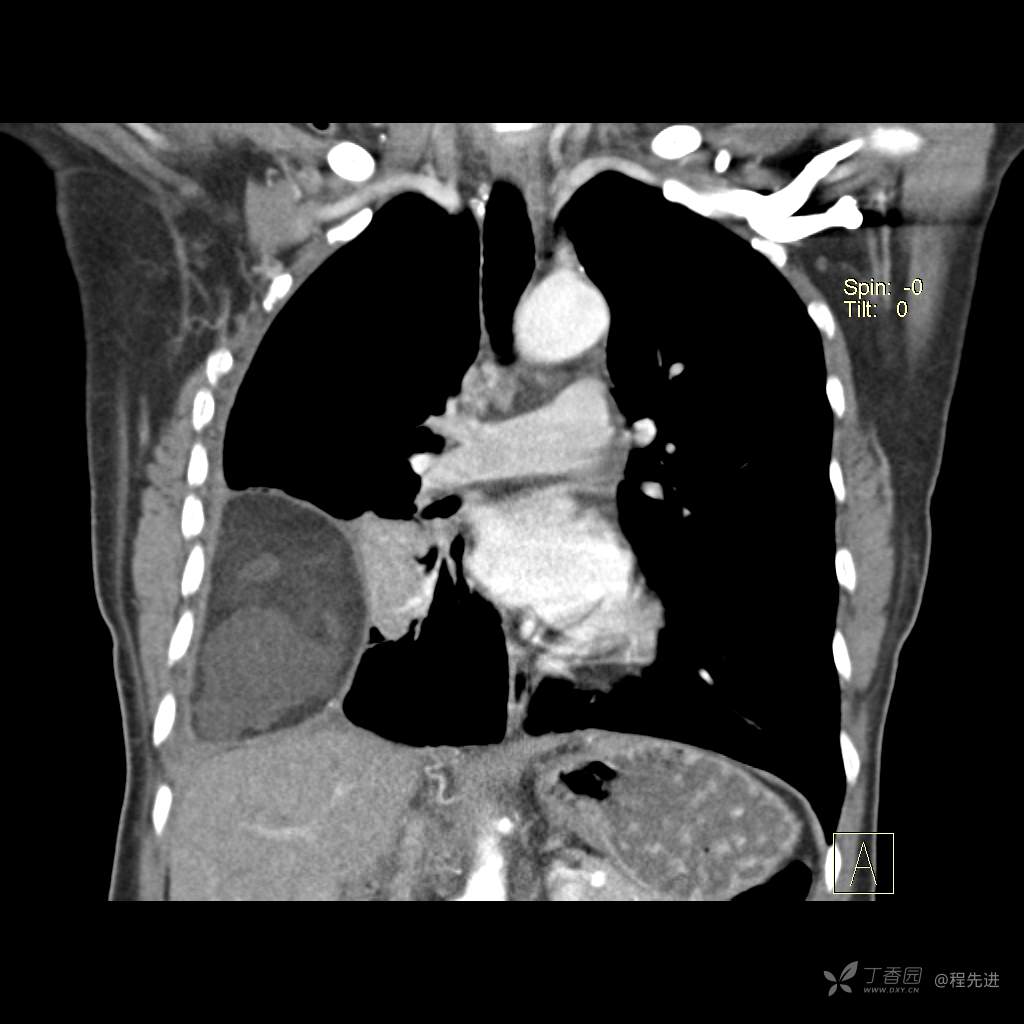

患者性别:女

患者年龄:51岁

简要病史:胸闷半年

肺淋巴管肌瘤病 (7)

乳糜胸 (8)